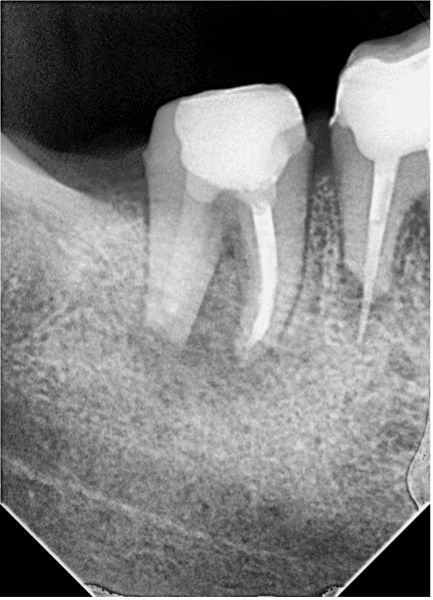

Hastamız 2. Seansa geldiğinde kalsin temizlendi. Apikal bölgedeki taşkın guta 3 boyutlu aktivasyon eğeleri ile çıkarıldı ancak eğeye ulaşılamadı ve kontrol filmi alındı (RESİM 6).

RESİM 6: Kırık eğenin konumu kontrol edildi.

Alınan radyografta eğenin konumu teyit edildi ve bölgedeki granülasyon dokusu ophtalmic forseps ile eğe görünecek şekilde temizlendi. Kanalın apikali paper pointle kurutulduğunda eğenin koronal kısmı görüldü ve tel ilmik tekniği ile çıkarma işlemine geçildi. Tel ilmik ile eğe kökün dışında yakalandı ancak yakalama sonucu eğe kökün uzun aksı boyunca 90 derece açı yapacak şekilde takıldı (RESİM 7) ve koronale çekilemedi.

RESİM 7: Tel ilmikle yakalanan eğe görseldeki gibi köke dik konumda kaldı